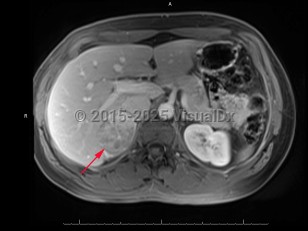

Adrenocortical carcinoma

An adrenocortical carcinoma is a rare (1 case per 1 million adults) malignant tumor of the adrenal cortex. The tumor is typically unilateral and may have an irregular shape. Adrenal carcinomas may be found incidentally on imaging or may be identified after a patient shows signs of endocrine dysfunction, such as hypercortisolism or virilization. About half of adrenal carcinomas do not produce hormones, while the other half produce any combination of the normal adrenal cortical hormones. Adrenal carcinomas have a bimodal epidemiology. They are most common in children aged younger than 5 years and in middle-aged adults. Syndromes such as multiple endocrine neoplasia type 1 are uncommonly the cause of adrenal carcinoma.

Adrenocortical carcinoma has a chronic duration, lasting years. Prognosis varies based on staging of the cancer; however, nearly half of all patients have metastases at the time of initial diagnosis.